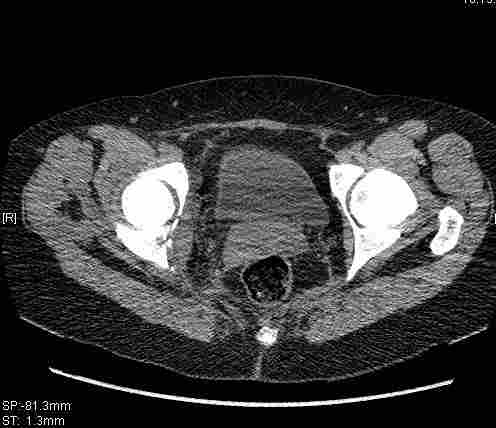

Удалось сегодня вывести пациентку в соседнюю больницу, где есть кт. Срезы сделаны только горизонтальные.